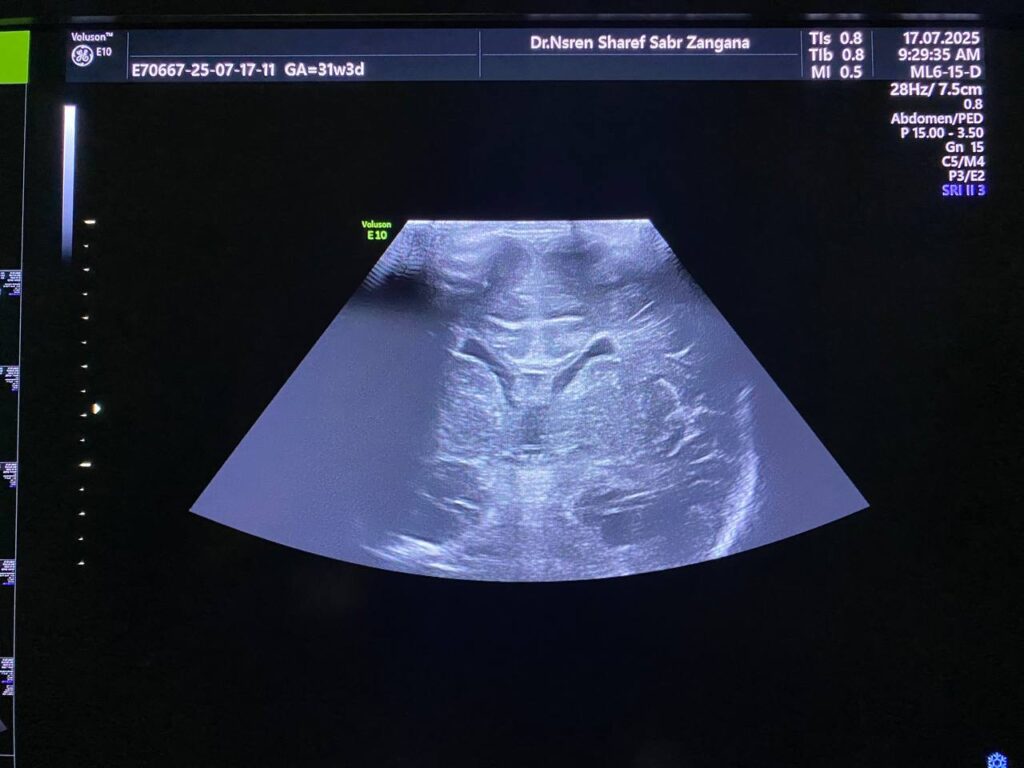

Mild hydrocephaly , maximum diamter of the posterior atrium of the lateral ventricles 16mm

Also mild dilated Third ventricle diamter 4.7mm , no dilated 4th ventricle seen , mostly due to mild stenosis at Sylvuis aqueduct